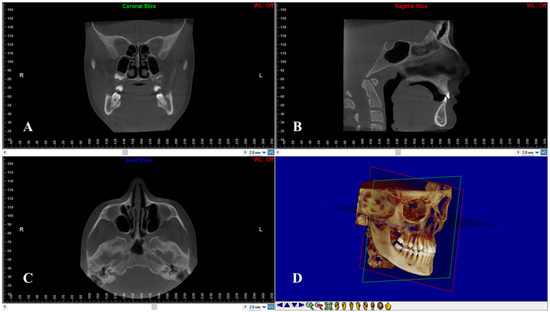

On multiple planar reconstruction images, the skull was reoriented to the Frankfort horizontal (FH) as follows (Figure 2): (1) in the frontal view, the mid-sagittal plane was fixed through the center of the anterior nasal spine (ANS), and the axial plane was constructed through both infraorbital skeletal landmarks; (2) in the right sagittal view, the axial plane was placed through the right porion and right infraorbital landmarks. For standardization, the left sagittal view was not processed to avoid orientation problems due to asymmetrically positioned portions; (3) in the axial view, the mid-sagittal plane was constructed through crista Galli and basion [23].

Figure 2.

Head re-orientation on coronal (A), sagittal (B) and axial (C) planes of CBCT scans. The 3D image (D) shows the head orientation on a 3D space.